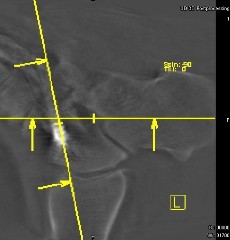

Abb. 1.

3-D-computertomographisches Bild mit Orientierungslinien für die 3-D-Rekonstruktion.